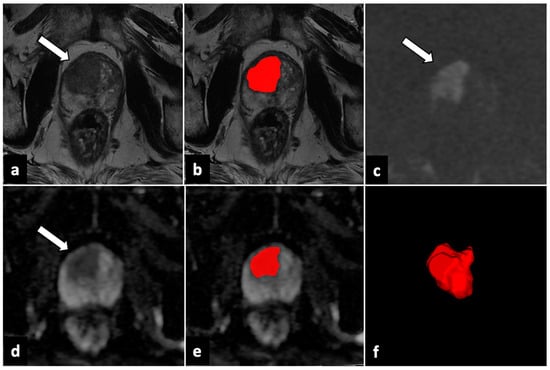

2.4. Image Analysis and Lesion Segmentation